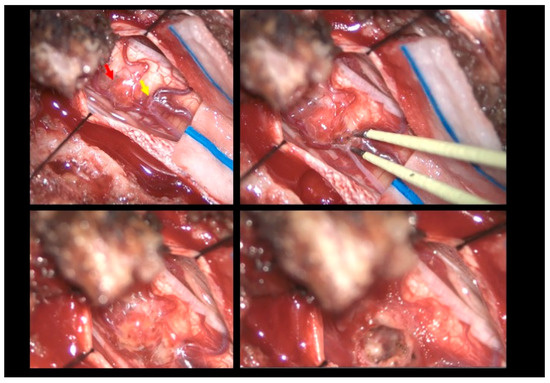

The patient was positioned prone, and a midline incision was performed, followed by bilateral muscle dissection and laminoplasty at T11–T12 using a piezoelectric osteotome (Mectron s.p.a—Carasco, Italy) [Figure 2]. Under the operating microscope, a dural opening was made, exposing the lesion, which appeared as an exophytic protrusion from the surface of the left posterior spinal cord, surrounded by a vascular malformation resembling a dural arteriovenous fistula (SDAVF) with multiple arteriovenous malformations on the pial surface [Figure 3]. Coagulation and disconnection of the fistulas were performed first by using bipolar cautery and scissor separation [Figure 3]; a detailed image of the hemangioma and the associated fistula is shown [Figure 4]. An incision was made around the lesion, which exhibited firm consistency. Due to the inability to remove the pathological tissue without traction, an ultrasonic aspirator was used for the microsurgical resection. Meticulous hemostasis was achieved. The dura mater was sutured, and a laminoplasty was performed using plates and screws. Standard wound closure was performed.

Figure 3.

Intraoperative findings. Upper left: Visualization of the hemangioma (red arrow) associated with the vascular malformation resembling a dural arteriovenous fistula (yellow arrow). Upper right: Sealing of the fistula using bipolar cautery. Bottom left: Macroscopic color change following fistula closure. Bottom right: Macroscopic appearance following hemangioma removal.